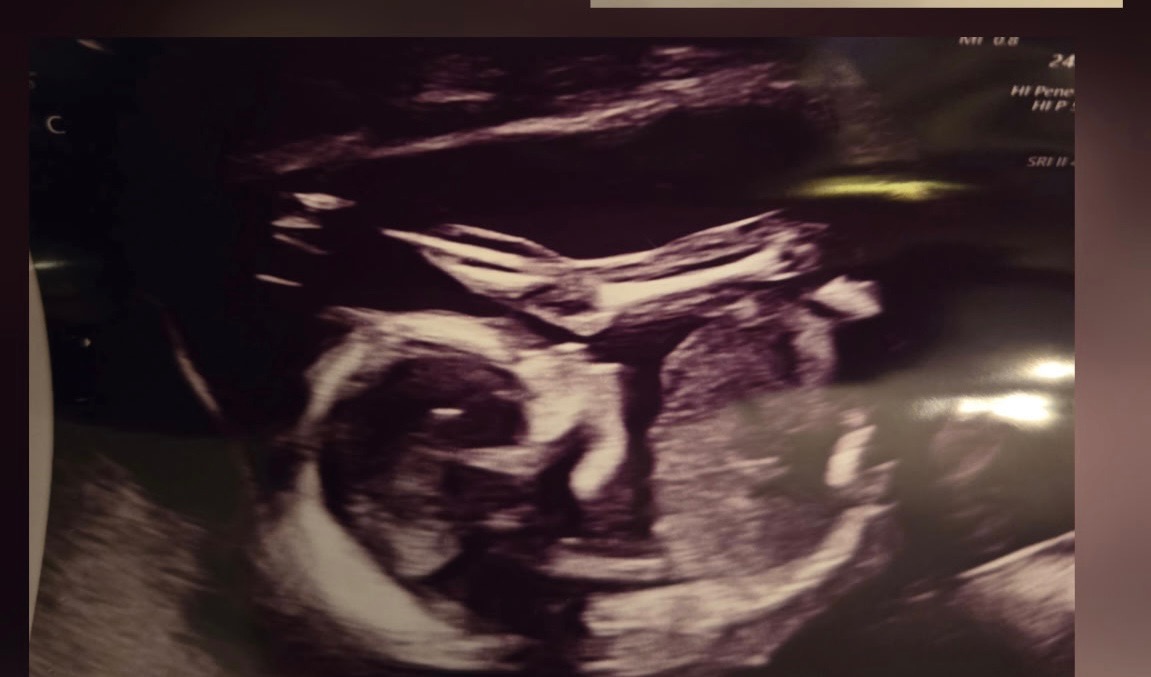

Jess is an amazing mother to her two young daughters, Hannah and Brooke, and a dedicated wife to the love of her life, John. They recently decided to expand their family and went through some fertility treatments. It was not IVF. She spontaneously released five eggs and all five were fertilized. Once again, this was not an intentional thing, nor is it something that could’ve been predicted. So now she is almost 20 weeks pregnant with quintuplets! For those of you who don’t know, that is five babies tucked safely away in her belly. The babies are thriving; they’re growing at appropriate rates, and as of right now, there’s no sign of major complications.